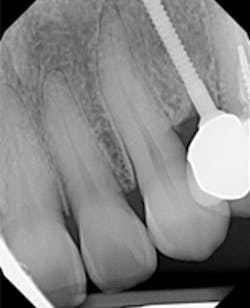

A 50-year-old female presented with a missing tooth No. 12 that was extracted for unknown reasons more than 10 years ago (figure 7). The patient was referred to our office for an implant consultation. Upon review of a CT scan, it was revealed that at the widest area buccal-lingually there was 4.09 mm and at the narrowest 3.8 mm (figure 8). She was presented with two treatment options: bone grafting or a narrow-diameter implant. She opted for the narrow-diameter implant, as it eased several of her concerns: she was unhappy with a removable appliance, worried about a block graft for a single tooth, and finances were a burden.

A 1.8 mm x 14 mm Anew implant (Dentatus) was selected, and a surgical guide was fabricated for a flapless approach. In this instance, a healing cap was placed, and the existing flipper was relieved to address financial concerns (figures 9 and 10). A screw-retained crown was fabricated three months post insertion (figures 11 and 12). The patient reported no postoperative discomfort, and the case remains successful, as shown in the two-year postoperative x-ray (figure 13).